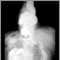

Hiatal hernia - X-ray

Heartburn is more likely to occur if you have a hiatal hernia, which is when the top part of the stomach protrudes upward into the chest cavity. This weakens the LES and makes it easier for acid to reflux from the stomach into the esophagus.